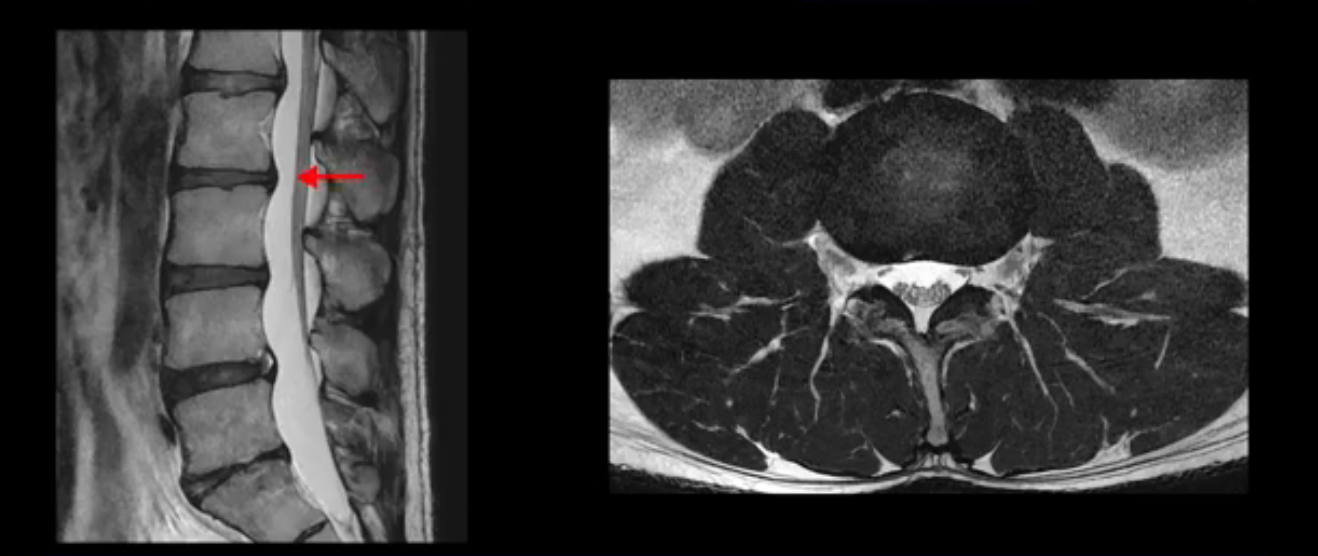

그런데 이분의 증상과 MRI가 전혀 일치하지 않는데, 왜 그런지 지금부터 자세히 설명드립니다. 이분 증상은 앉으면 엉치와 허리가 심하게 아파 10분 이상 앉는 게 어렵고 양쪽 발가락이 앉아있을 때나 누워있을 때 다 저립니다. 걸을 때도 아파서 10분 걷기도 어렵습니다. MRI를 마디마디 살펴보면 1번 2번은 오른쪽으로 살짝 밀려나온 디스크가 있지만 전혀 심하지 않고, 뒤에 또 설명하겠지만 최근에 밀려나온 급성 디스크가 아니고 오래된 디스크로 판단됩니다.

2번 3번도 비교적 디스크 상태는 좋고 신경 구멍 넓이도 아주 넓습니다.

3번 4번도 마찬가지로 디스크상태 좋아 보이고 신경 눌림 전혀 없어 보입니다.